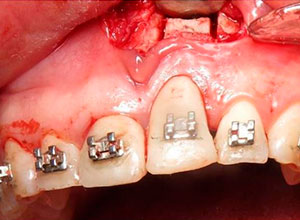

Decidimos hacer una corticotomia alveolar, dejando tejidos blandos en su lugar y cambiar la corona de cerámica por una corona de acrílico para cementar bien los brackets y poder empezar con la distracción.

Después de la corticotomia dejamos un tiempo de siete días para que se organizaran las células tisulares.

Se empezó a hacer la distracción, primero con un arco recto y posteriormente con elásticos haciendo el recorte con el borde incisal conforme se va bajando el implante con el bloque óseo.